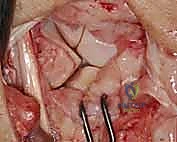

- Joint Inspection: With the capsule opened, we can now directly visualize the midcarpal and radiocarpal joint surfaces. Take a moment to thoroughly examine these for any arthritic changes, chondral damage, or other intercarpal pathology that might influence our repair strategy.

TECH FIG 5 • E. Midcarpal and radiocarpal joint surfaces exposed and examined for arthritic changes.

Now, direct your attention specifically to the **scapholunate and lunotriquetral ligaments**. Thoroughly examine the dorsal aspect of the lunotriquetral ligament. Assess its integrity, quality, and whether it appears suitable for direct repair. We're looking for clean tears that can be reapproximated versus attenuated, frayed tissue that would necessitate reconstruction. Perform dynamic stress tests under direct visualization to confirm the degree of instability.